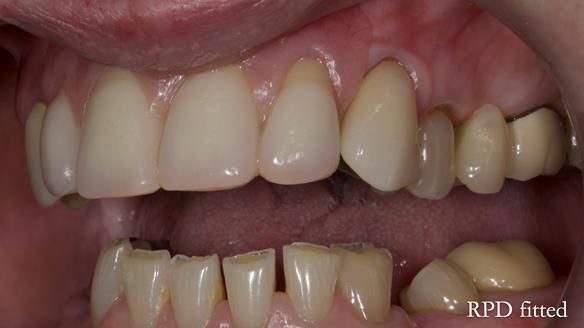

This is one of those cases that reminds me why I love removable prosthodontics. Pam was an absolute joy to treat — we were on the same page throughout. Her old upper flexible denture was loose, uncomfortable, and unaesthetic. We replaced it with a carefully designed metal-based upper partial denture/splint and new porcelain-bonded-to-zirconia (PBZ) crowns for the canines. The result is stable, comfortable, and natural-looking.

- Diagnosis and plan – Flexible upper denture ill-fitting with poor stability, retention, and appearance. Plan: metal-based upper partial denture/splint with lighter porcelain-bonded-to-zirconia crowns on UR3 and UL3.

- Fit and reviews – fit of the denture/splint and new crowns, followed by reviews to fine-tune comfort and function. Ongoing support and one-year warranty.

The result

- Better support for lips and lower face.

- Natural smile and improved chewing.

- Designed to protect remaining teeth.

- Future additions possible if needed.